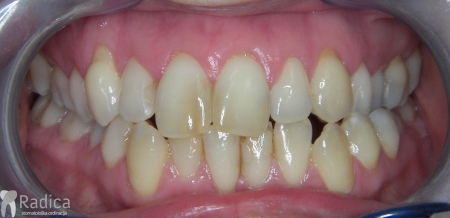

Slučaj 4: ispravljanje kompresije Invisalign full terapijom